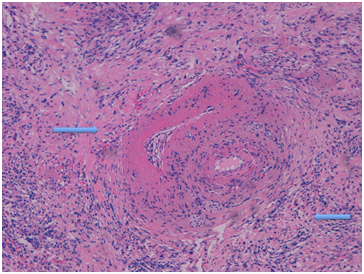

Assumptions physiopathology immuno-allergic: Late APS diagnosis, causes a bleeding subcapsular splenic infarct uninterruptedly to pancreatic tail, which acts antigenic trigger and triggers immune activation first cell helper Th2, and later of regulatory T cells (Treg) with over-expression Interleukins 4, 5, 10 and 13, along with TGF-Beta. This leads to eosinophilia, elevated IgE and IgG4 and fibrosis progression characteristic IgG4 related disease. Picture: inflammatory pseudo-tumour and A.P: storiform fibrosis, obliterated phlebitis and plasma cell infiltration IgG4 (Figure 4).

Figure 4 Inflammatory pseudo tumor and AP: storiform fibrosis, obliterative phlebitis and plasma cell infiltration IgG4.